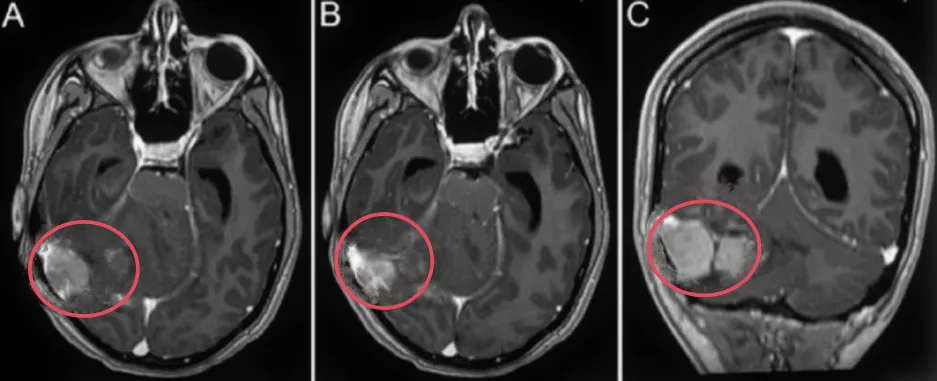

髓母细胞瘤包括一系列发生在后颅窝的肿瘤亚群。这种恶性肿瘤主要发生在婴儿和儿童,中位年龄为8岁,男女比例为1.5:1。它约占全部儿童脑肿瘤的20%,是较常见的儿童脑肿瘤。然而...